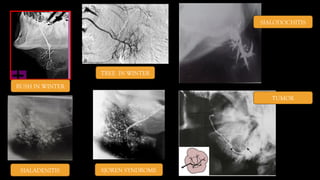

Interpretation

 Normal salivary gland is that of a leafless tree.

 This radiograph shows the main duct gradually going in secondary branches and then into tertiary

branches.

 Chronic Recurrent Sialadenitis:

 Shows focal narrowing of the main duct and central ductal dilation (Sialectasia), these dilated ducts

often taper down dramatically to normal peripheral ducts.

 Sjögren’s syndrome usually results in the punctate filling defects initially and then mulberry tree

appearance on the sialogram

BUSH IN WINTER

TREE IN WINTER

SIALODOCHITIS

SIALADENITIS SJOREN SYNDROME

TUMOR